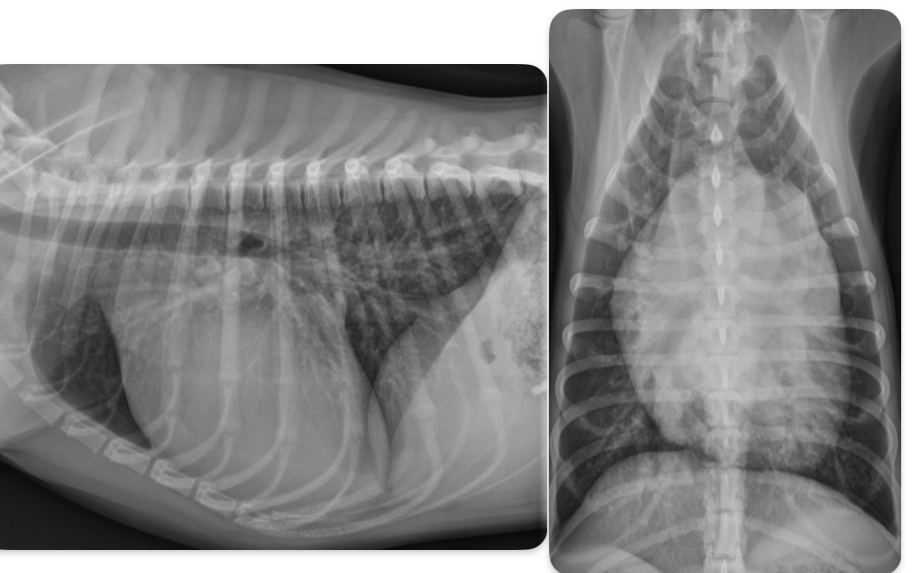

Roentgen signs of pulmonic stenosis

-Right heart enlargement (RVE +/- RAE) d/t PRESSURE OVERLOAD

-MPA enlargement

-Normal to small pulmonary vessels (hypoperfusion)

+/- RHF

What disease does this dog have

Pulmonic stenosis